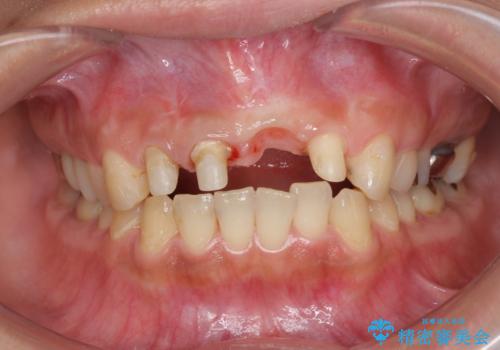

- 前歯の見栄えの悪さの改善を求めて来院されました。

左側の前歯には他院で埋入されたポジションの悪いインプラント補綴により歯冠長の長いクラウンが装着されており、感染による排膿も認められこのまま審美性を改善するのは難しい状態です。

感染したインプラントからは排膿が間欠的に認められ、掻爬・除去が検討されうるような状況でした。